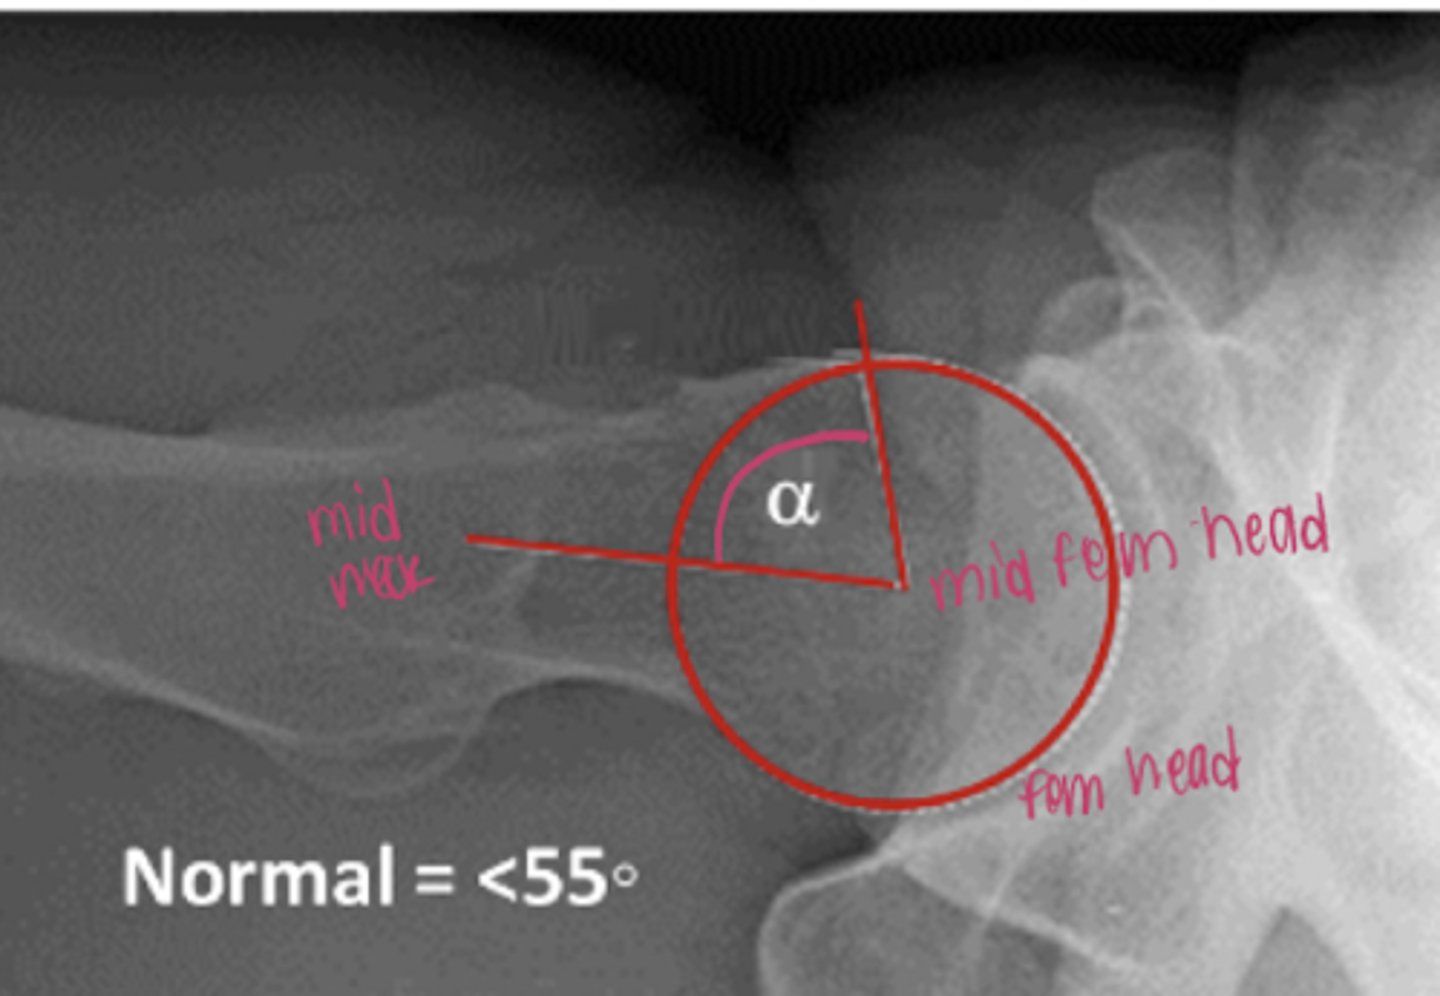

alpha angle

used to diagnose FAI CAM (large femoral head)

alpha angle > 55